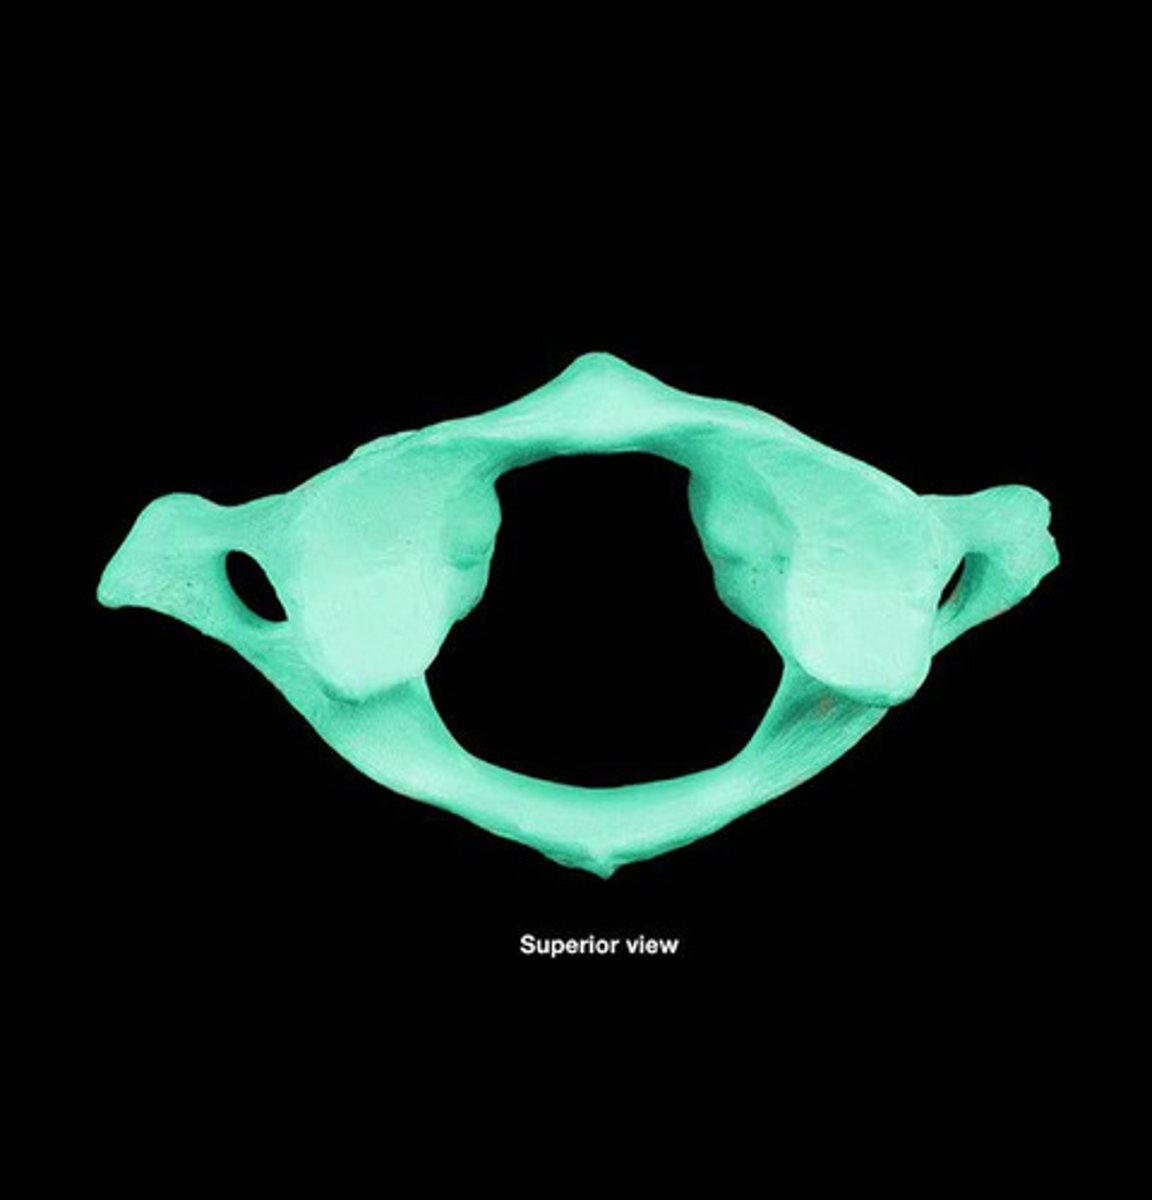

Atlas

"Yes motion"